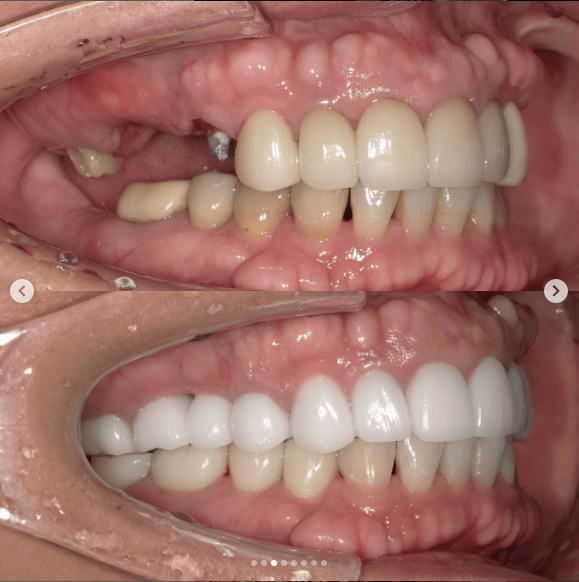

「ずっと放置してしまっていた。今回はちゃんとしっかり治したい」ということで、強い意志をもって来院してくださった患者様の症例です。

インプラント治療、セラミック治療、歯周病治療により、審美性と機能、咬みあわせの再建を行いました。

患者様は咬みあわせの確立により、食事もしやすく、普段の顎関節の状況も良くなり、機能の回復にも満足してくださり、また審美性も喜んでくださいました。

放置期間が長くだいぶ骨が溶けてしまっていたので、前歯部のインプラントは骨の再生療法などが必要だったりしましたが、患者様が治療への前向きな姿勢をだしてくださっていましたので期間も最短で終わりました。

一度放置してしまうと、億劫になってしまってなかなか行動に移すのは難しいと思いますが、少しでも早く治してあげた方が毎日の食事も楽になりますし、お顔の見栄えもお顔の骨格の歪みも改善します。